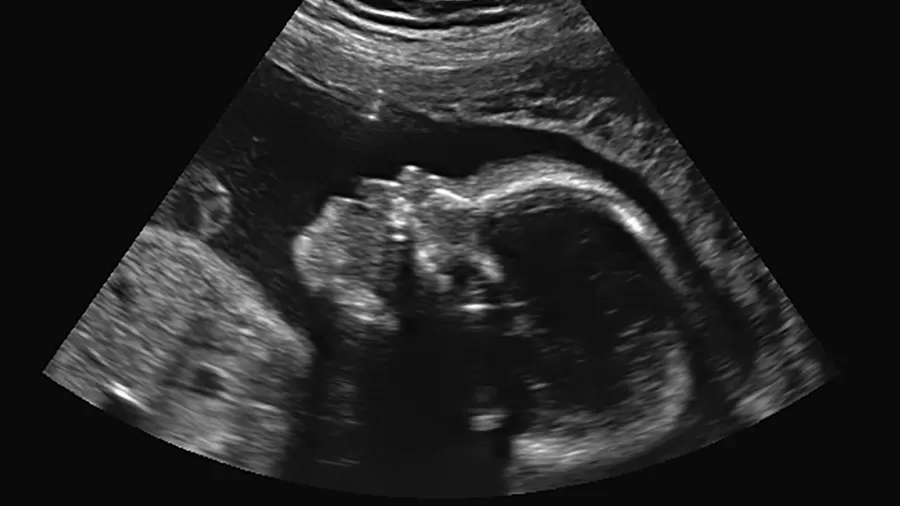

Olha que notícia boa: pela primeira vez, uma bebê diagnosticada no útero com Atrofia Muscular Espinhal (AME), passou por um tratamento, nasceu saudável e sem sinais aparentes da condição.

A intervenção pioneira ocorreu por cientistas do St.Jude Children’s Research Hospital, nos Estados Unidos, e foi divulgada no New England Journal of Medicine.

O tratamento utilizou o medicamento risdiplam, administrado de forma oral à mãe durante as últimas seis semanas de gestação. Hoje, a bebê já tem dois anos e meio, e apesar de não apresentar sinais, continua sob acompanhamento médico.